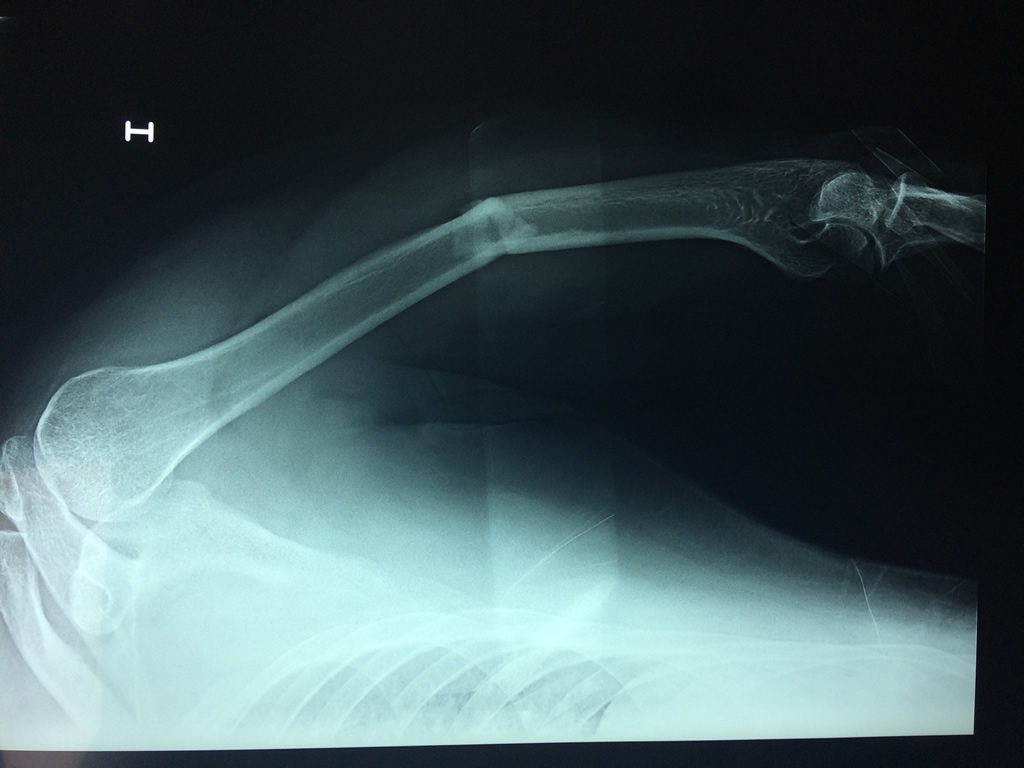

Cirugías de Cadera

El Húmero (en latín, humerus) es el hueso más largo de las extremidades superiores en el ser humano. Forma parte del esqueleto apendicular superior y está ubicado en la región del brazo. ... El extremo proximal del húmero tiene la cabeza, cuellos quirúrgico y anatómico y tubérculos mayor y menor.